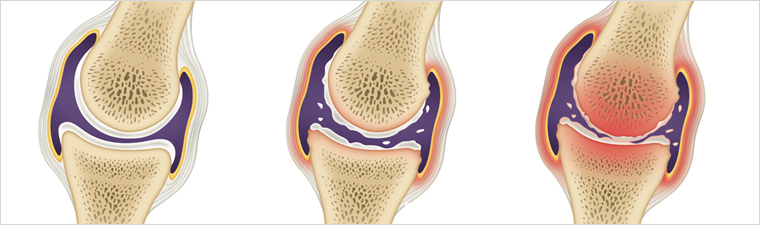

3. 고관절 통증 증상 - 퇴행성 고관절염

연골이 닳으면서 관절 사이 간격이 줄어들고 통증과 강직이 나타납니다. 초기에는 소염진통제나 연골 보호제, 휴식과 적절한 운동으로 경과를 관찰하며 보존적 치료를 시도합니다. 보존적 치료로 증상이 호전되지 않거나 기능 저하가 심하면 수술적 치료를 고려할 수 있습니다.

5. 퇴행성 관절염

연골 보호층이 닳아 없어지면 뼈와 인대에 손상이 발생하고 염증과 만성 통증이 생깁니다. 연골 손상으로 인한 통증은 회복이 더디므로 조기 관리가 필요합니다.